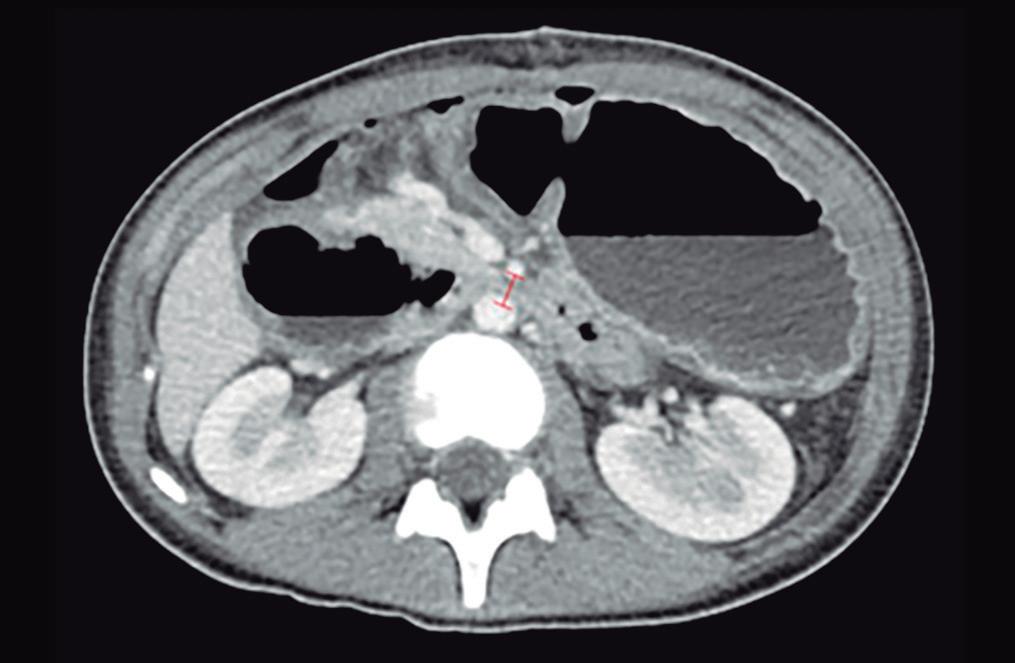

Obstrucción intestinal duodenal en una adolescente femenina

Duodenal Bowel Obstruction in a Teenage Female Patient